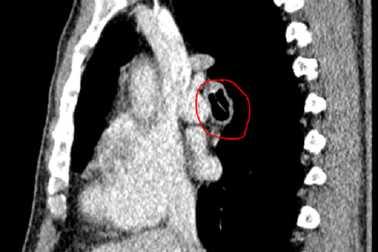

Ho sặc sụa suốt 3 năm vì xương cá lọt vào phế quảnSuốt 3 năm qua, người đàn ông 55 tuổi phải sống chung với những cơn ho sặc sụa, đàm nhớt, đi khám nhiều nơi nhưng không tìm ra bệnh. Sau khi kiểm tra hình ảnh, bác sĩ tiến hành nội soi gắp ra mảnh xương cá từ phế quản của ông.